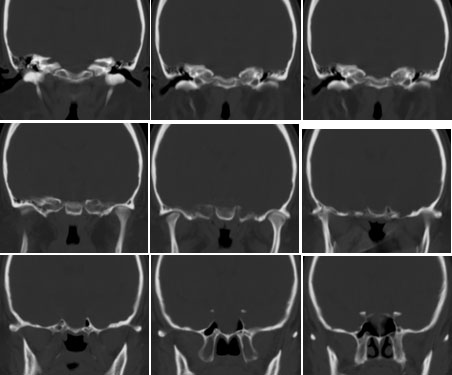

鞍区垂体窝内见一巨大类椭圆性软组织块影,前后床突受压移位、变薄,鞍底凹陷,应当能明确诊断垂体瘤。不过最好能做个mri看看视神经受累情况

蝶鞍内圆形密度不均匀,包膜完整肿块影,前床突与鞍底变薄.

意见:垂体大腺瘤.

本病例单凭ct检查是很难定位准确的,是鞍上病变侵犯鞍内、还是鞍内病变向鞍上生长?

1、如果鞍内肿瘤突破鞍隔,向鞍上生长,考虑垂体腺瘤,其典型表现是肿瘤呈"8"字征。

2、如果是鞍上肿瘤侵犯鞍内,要考虑鞍区脑膜瘤、生殖细胞瘤、实性颅咽管瘤(多为囊性、少数也可实性)、转移瘤、垂体柄胶质细胞瘤。